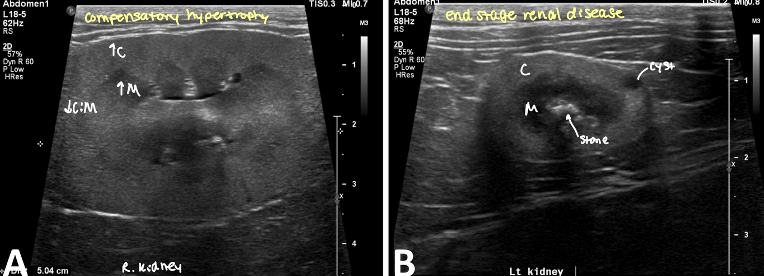

condition where one kidney becomes enlarged to compensate for a down kidney

compensatory hypertrophy

kidney preserved architecture

decreased CM distinction

acute vs chronic pyelonephritis rad and ultrasound findings

acute

slight enlargement of kidneys ± RP effusion

smooth contours and diffusely hyperechoic

↓CM distinction

pus/echogenic content in pelvis

pyelectasia

Chronic

small to normal sized kidneys with irregular shape

pelvis distorted

small, irregularly lumpy, bumpy shaped kidneys, ↓CM distinction ± mineralization

end stage kidneys